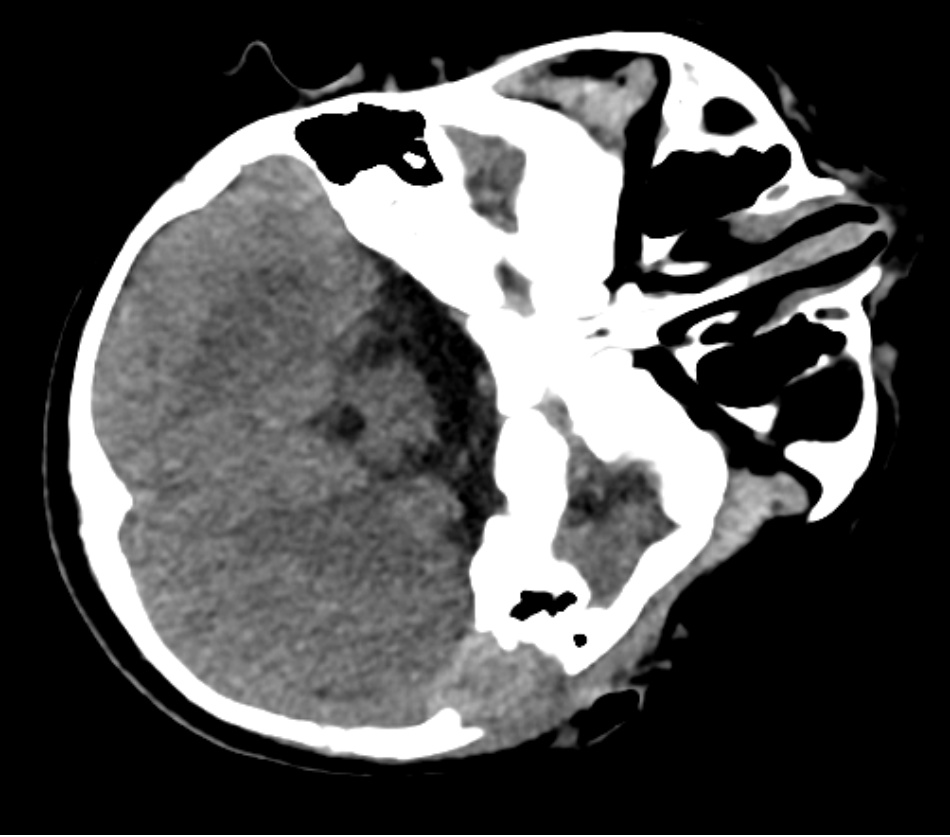

辅助检查:1) 血白细胞(WBC) 15.42 × 109/L ↑ (4.8~14.6 × 109),淋巴细胞(LYM#) 9.72 × 109/L ↑ (2.5~9 × 109),C反应蛋白(CRP1) 45.05 mg/L ↑ (0~10)。2) 体表包块彩超(图1)示:左耳后所述处下方可见范围约为2.4 × 1.8 × 2.0 cm低至无回声区,边界清,回声不均,内见密集点状回声,CDFI:其内及周边可见血流信号。3) 硬性耳内镜检查(图2)示:左侧外耳道充血肿胀,外耳道见白色分泌物,鼓膜窥不到;右外耳道通畅,稍充血,见少许分泌物,鼓膜完整。4) 颞骨CT (图3)示:左侧颞骨乳突部骨质破坏,左侧乳突气房显示欠清,局部见团块状软组织密度灶,密度欠均,边界欠清,较大截面约2.3 cm × 1.8 cm,CT值约为33~45 HU:左侧耳后软组织稍肿胀,左侧外耳道壁增厚,左侧鼓膜增厚。右侧外耳道未见明显异常。右侧乳突气房气化可。双侧中耳鼓室、右侧乳突窦腔清晰,腔内未见明显异常高低密度影。双侧听小骨未见明显异常。双侧内耳和内听道未见明显异常。

Figure 1. The described area posterior to the left auricle demonstrates a hypoechoic to anechoic lesion measuring approximately 2.4 × 1.8 × 2.0 cm. Its borders are well-defined, its internal echotexture is heterogeneous, and it contains dense punctate echoes. Color Doppler Flow Imaging (CDFI) reveals the presence of blood flow signals within the lesion and in its peripheral regions

1. 左耳后所述处下方可见范围约为2.4 × 1.8 × 2.0 cm低至无回声区,边界清,回声不均,内见密集点状回声;CDFI:其内及周边可见血流信号